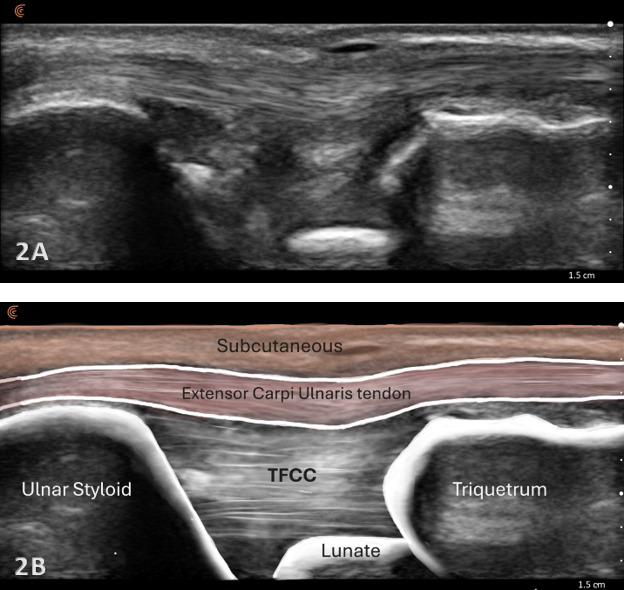

Normal Sonographic Appearance

Normal TFCC appears as a thin, continuous, triangular band of homogeneous echogenicity extending from the distal ulna toward the ulnar carpal bones. The margins are smooth and well defined, without fiber disruption or adjacent fluid collection. No abnormal gapping is observed at the ulnocarpal interface, and the surrounding joint recess remains collapsed in the absence of effusion.